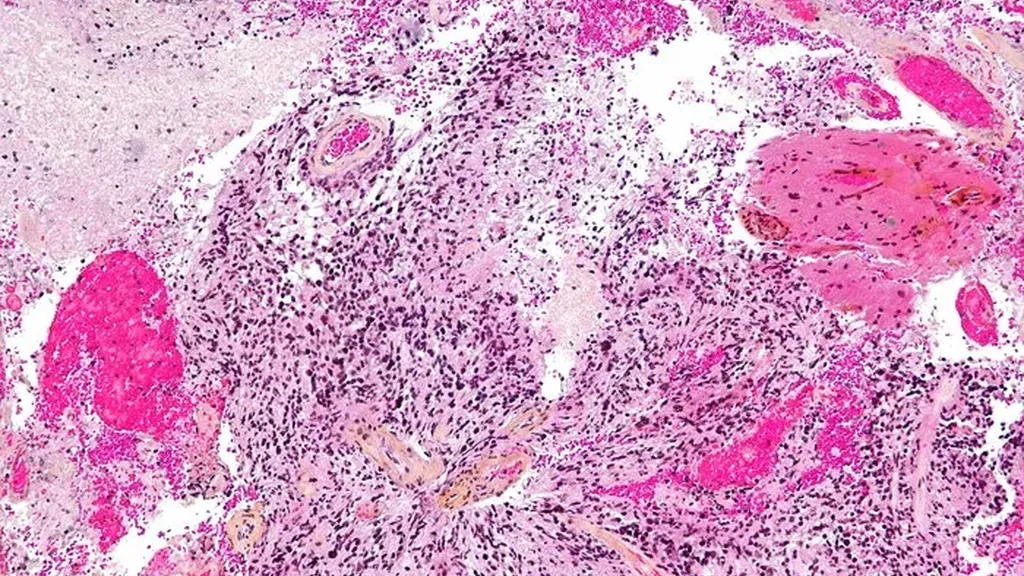

Il glioblastoma è un tumore cerebrale a crescita rapida che si sviluppa a partire dalle cellule gliali del cervello, quelle che supportano e sostengono i neuroni, e si stima che colpisca circa 15mila persone ogni anno. “Il glioblastoma è il tumore cerebrale più letale, con una sopravvivenza media di soli 12-16 mesi dal momento della diagnosi nonostante le terapie”, osserva Huali Su, primo firmatario dello studio coordinato da Deliang Guo: “C’è urgente necessità – aggiunge Su – di nuovi bersagli molecolari per questa malattia”.